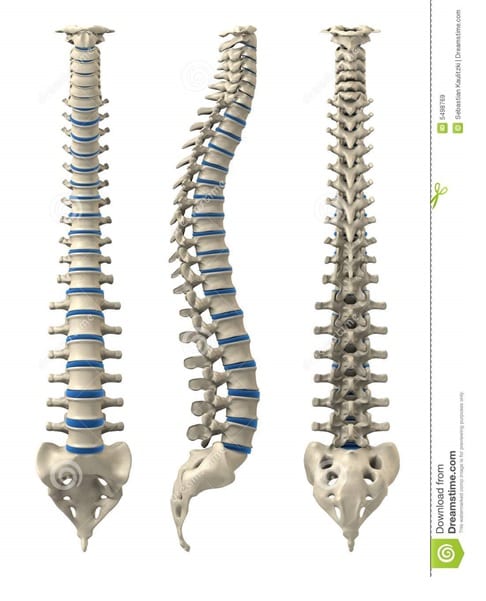

- dyskopatia kręgosłupa lędźwiowo- krzyżowego i szyjnego

Dyskopatia kręgosłupa lędźwiowo-krzyżowego i szyjnego

Z czego może wynikać: z patologii dysków międzykręgowych, z patologii więzadłowej, ze skrzywienia (wrodzonego, nabytego), z kręgozmyku lub z patologii mięśni przykręgosłupowych.

Co jest bezpośrednią przyczyną?

- charakter wykonywanej pracy

- nadmierne przeciążenia lub brak ruchu

- urazy

- nadwaga

- genetyka

- styl życia- nawyki

- stres

- choroby przewlekle np. reumatoidalne, kręgozmyk wrodzony

Dlaczego dyskopatia dotyka kobiety w ciąży?

Dlaczego dyskopatia dotyka kobiety w ciąży?

- wpływ relaksyny

- wpływ większej wagi ciała

- zmiana mechaniki ciała i kręgosłupa

- ucisk na struktury kostne i nerwowe przez rozwijający się organizm dziecka